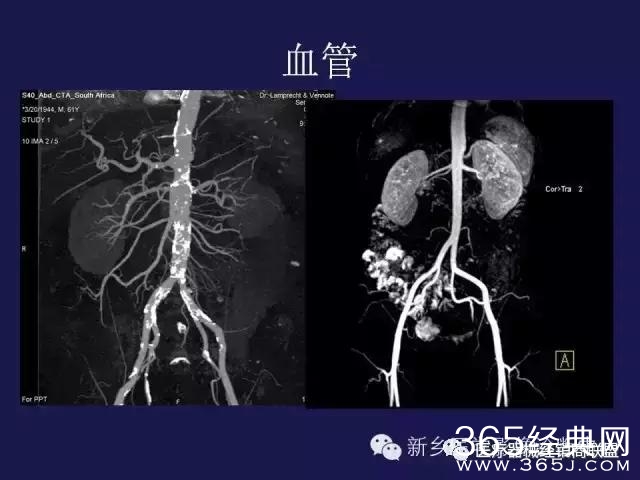

CT、MRI很难?NO,今日我们一起来学习一下如何读CT、MRI!

内行看门道: